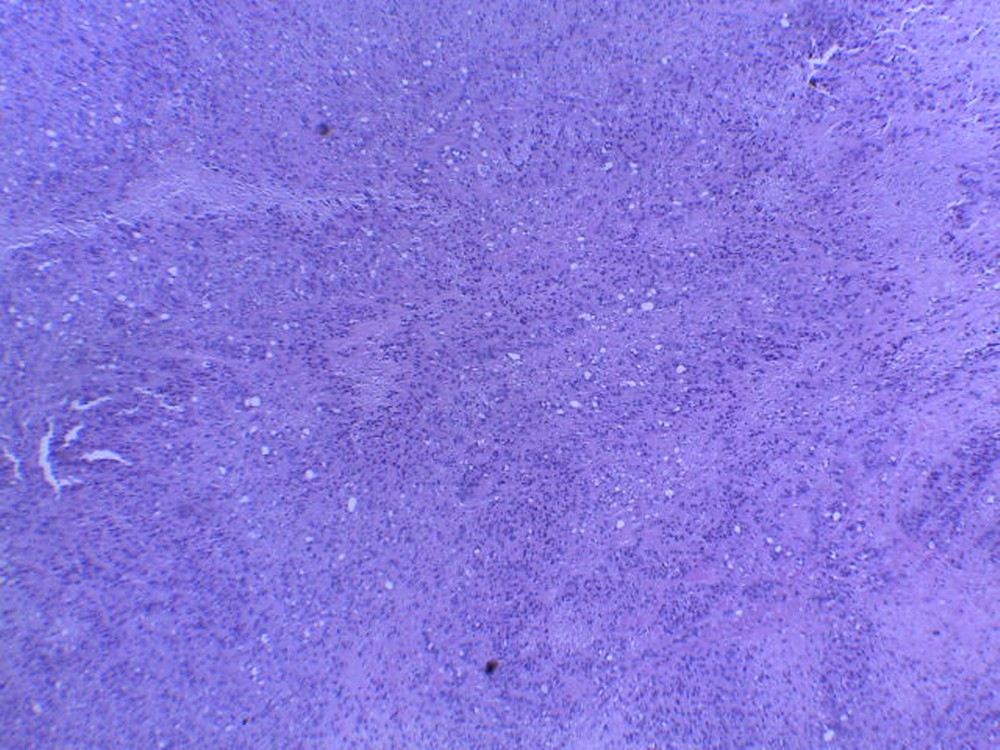

Caso del mes de Febrero de 2021

Mujer de 39 años con tumor en tobillo.

Respuesta:

Hemangioendotelioma epitelioide.